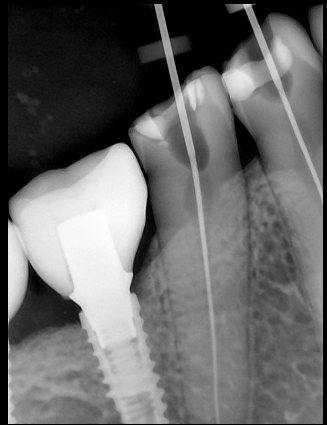

CR/DR 牙齿分割阶段记录

当前进展

- 完成了 CR/DR 牙齿相关分割训练

相关测试

遇到的问题

- 训练过程中出现过 mask 下移问题

- 部分结果会出现 box 填充异常

- mask 边缘仍然有比较明显的锯齿感

参考